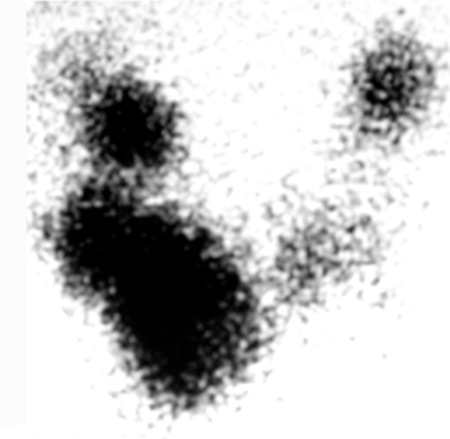

A varredura mostra áreas de captação elevada e diminuída, indicando nódulos funcionantes e não funcionantes.[1][Figure caption and citation for the preceding image starts]: Cintilografia de tireoide mostrando captação variegada no bócio multinodular tóxicoCortesia da Dra. Elizabeth Pearce [Citation ends].com.bmj.content.model.Caption@7cd9f5f4 Geralmente, a captação é normal.